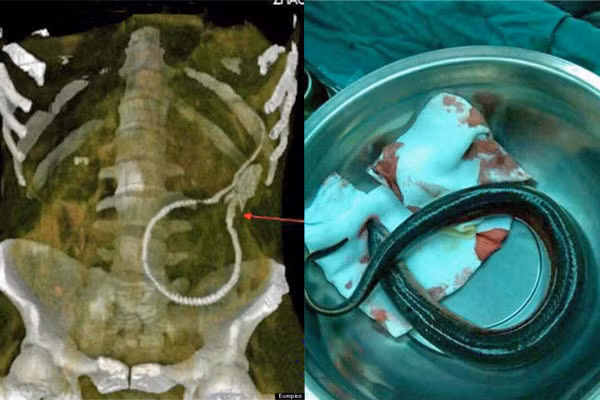

Lươn trong hậu môn

Một người đàn ông Trung Quốc sau khi xem phim khiêu dâm đã nhét một con lươn dài 51cm vào bên trong hậu môn. Con vật đã cắn vào thành ruột già bệnh nhân trong quá trình cố gắng trốn thoát khỏi số phận khắc nghiệt, rút cục con lươn bị mắc kẹt trong ruột già của người đàn ông trên.